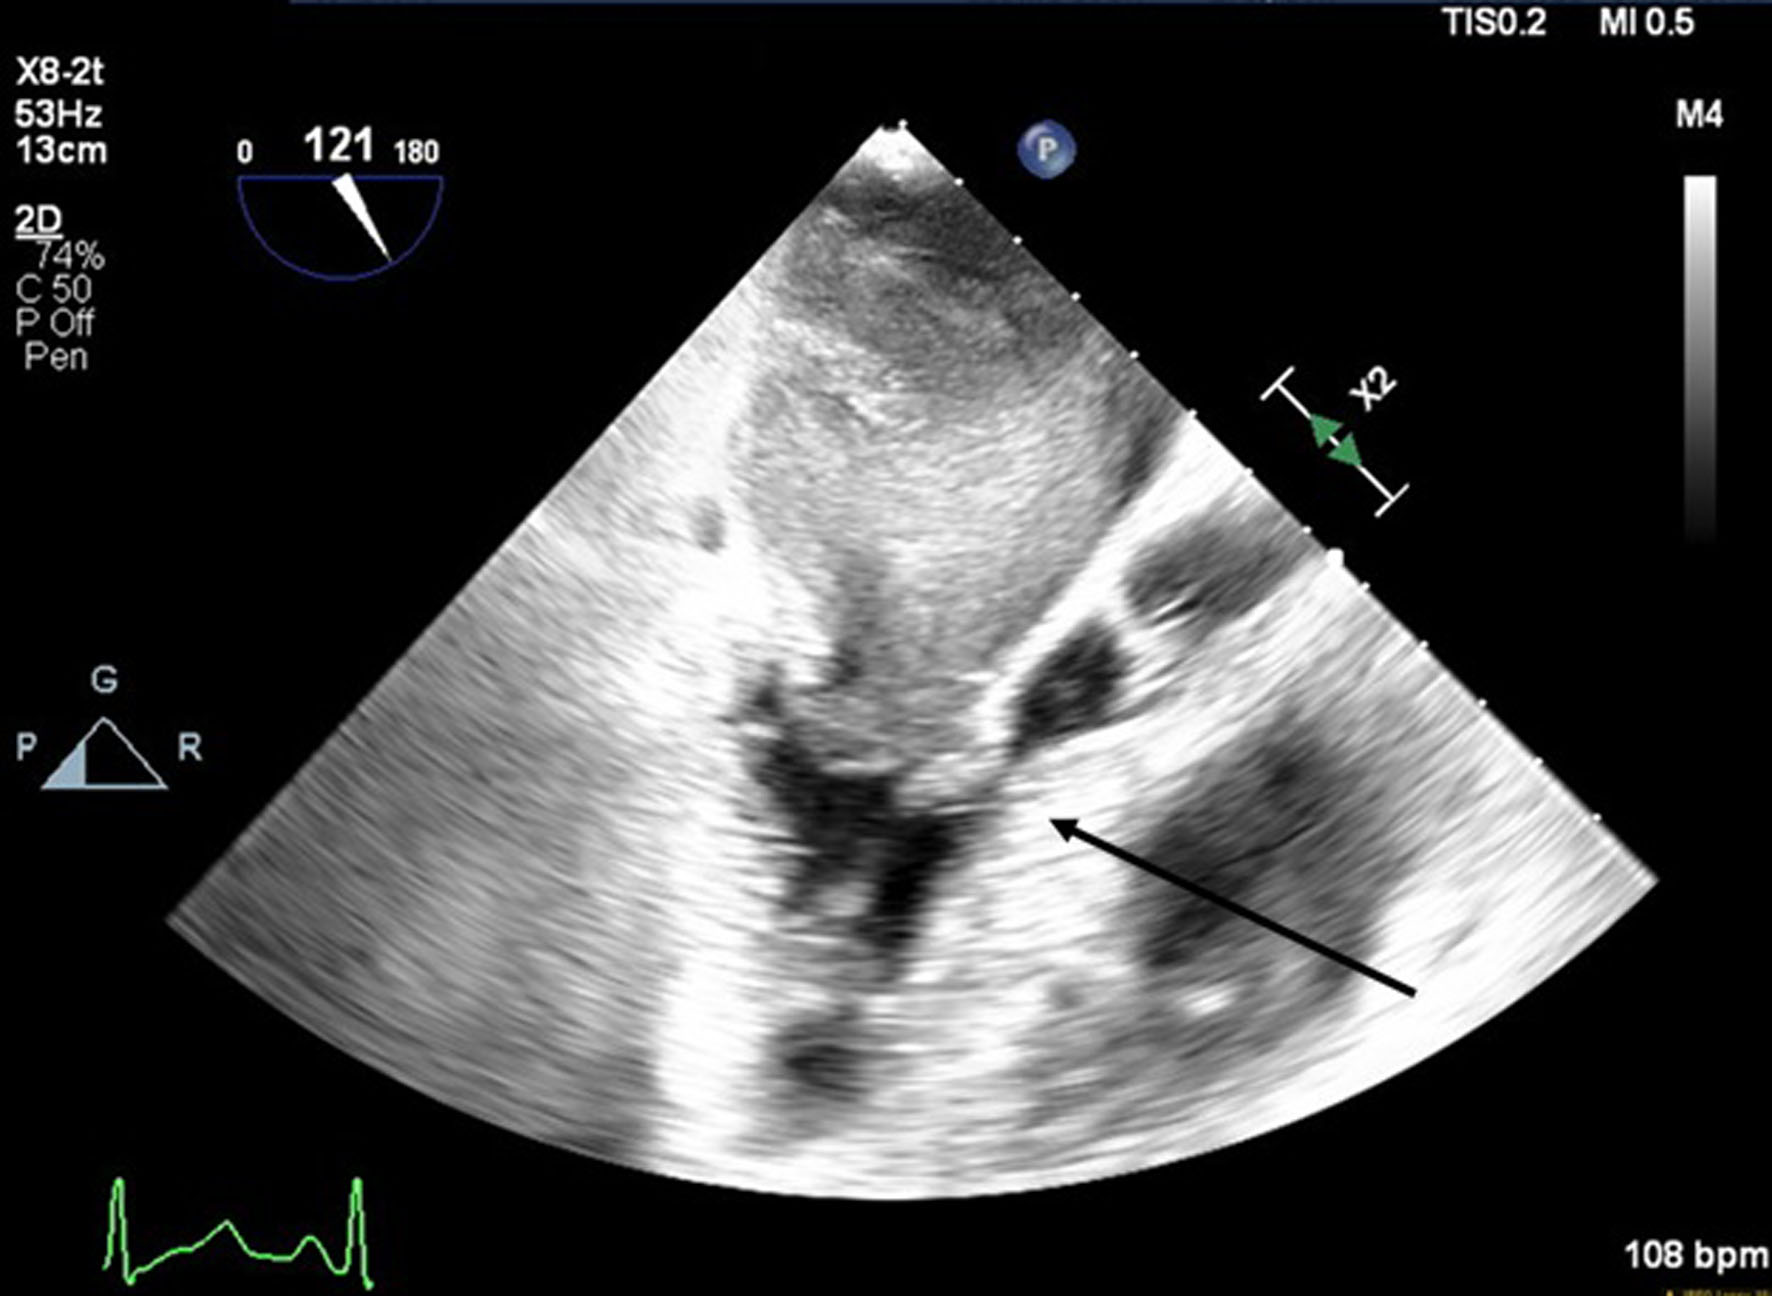

A 66-year-old obese woman presented to the emergency department (ED) with a 2-month history of progressive fatigue, 20-lb weight loss, orthopnea, wheezing, chest pressure, lower extremity edema, dyspnea on exertion, and paroxysmal nocturnal dyspnea. On examination, she had a systolic murmur. Transthoracic echocardiography (TTE) revealed a 5-cm mass occupying her left atrium. Right and left heart catheterization showed no flow-limiting coronary artery disease. Right heart pressures were as follows: right atrium 3 mm Hg, right ventricle 66/4 mm Hg, pulmonary artery 67/25 mm Hg, pulmonary capillary wedge pressure 25 mm Hg, and left ventricle 103/9 mm Hg. With plan for further workup, she was discharged and scheduled for elective resection. She returned to the ED 5 days later with severe acute hypoxic respiratory failure. On admission, vitals were as follows: heart rate (HR) 129, respiratory rate (RR) 44, SpO2 92%, and blood pressure (BP) 110/70. Her hypoxemia was managed with high-flow nasal cannula, and she was scheduled for urgent resection of her left atrial mass. In the operating room, she was severely orthopneic when the head of her bed was lowered below 90°. A radial arterial and internal jugular central venous catheter were placed while she was in a seated position on high-flow nasal cannula (fraction of inspired oxygen (FiO2) 100%, 35 liters per minute (LPM)). Femoral central venous and arterial cannulas were also placed prior to induction of anesthesia to enable emergent transition cardiopulmonary bypass (CPB). A dexmedetomidine infusion was used to facilitate vascular cannulation, surgical preparation, and draping. Vasopressin, epinephrine, and norepinephrine infusions were started preemptively, and she received a 250-mL albumin bolus. Her airway was secured with video laryngoscopy after induction with etomidate and rocuronium. After induction, she became profoundly hypotensive and hypoxemic, with mean arterial pressure (MAP) dropping by 30 mm Hg and oxygen saturation dropping to 70%. This brief episode resolved with administration of crystalloid, vasopressin boluses, and Trendelenburg positioning. Despite a transient period of hypotension and hypoxia, emergency CPB was not required. A median sternotomy was performed, and she was transitioned to CPB by aorto-bicaval cannulation. Intraoperative transesophageal echocardiography (TEE, X8-2t, EPIQ CVx; Philips Ultrasound, Bothell, WA) redemonstrated a large pedunculated mass traversing the interatrial septum and occupying the right and left atria. Mid-esophageal views were used to image the large heterogeneous mass (Figs. 1, 2). She was found to have a 7 × 4.5 cm left atrial mass arising from the lateral wall of the atrium near the left inferior pulmonary vein. Pulmonary venous return was obstructed, likely contributing to her pulmonary hypertension, pulmonary edema, and hypoxemia. During atrial systole, the mass traversed the mitral valve orifice and obstructed mitral inflow and the left ventricular outflow tract (LVOT). LVOT obstruction persisted during early ventricular systole, and flow acceleration was observed with color flow doppler (Figs. 3-5).

Figure 2. Mid-esophageal four-chamber view. A mass occupies the majority of the left atrium during systole. The arrow denotes the large cardiac tumor.

Figure 3. Mid-esophageal aortic long-axis view showing a mass obstructing the left ventricular outflow tract (LVOT) during early systole. The arrow indicates LVOT obstruction.